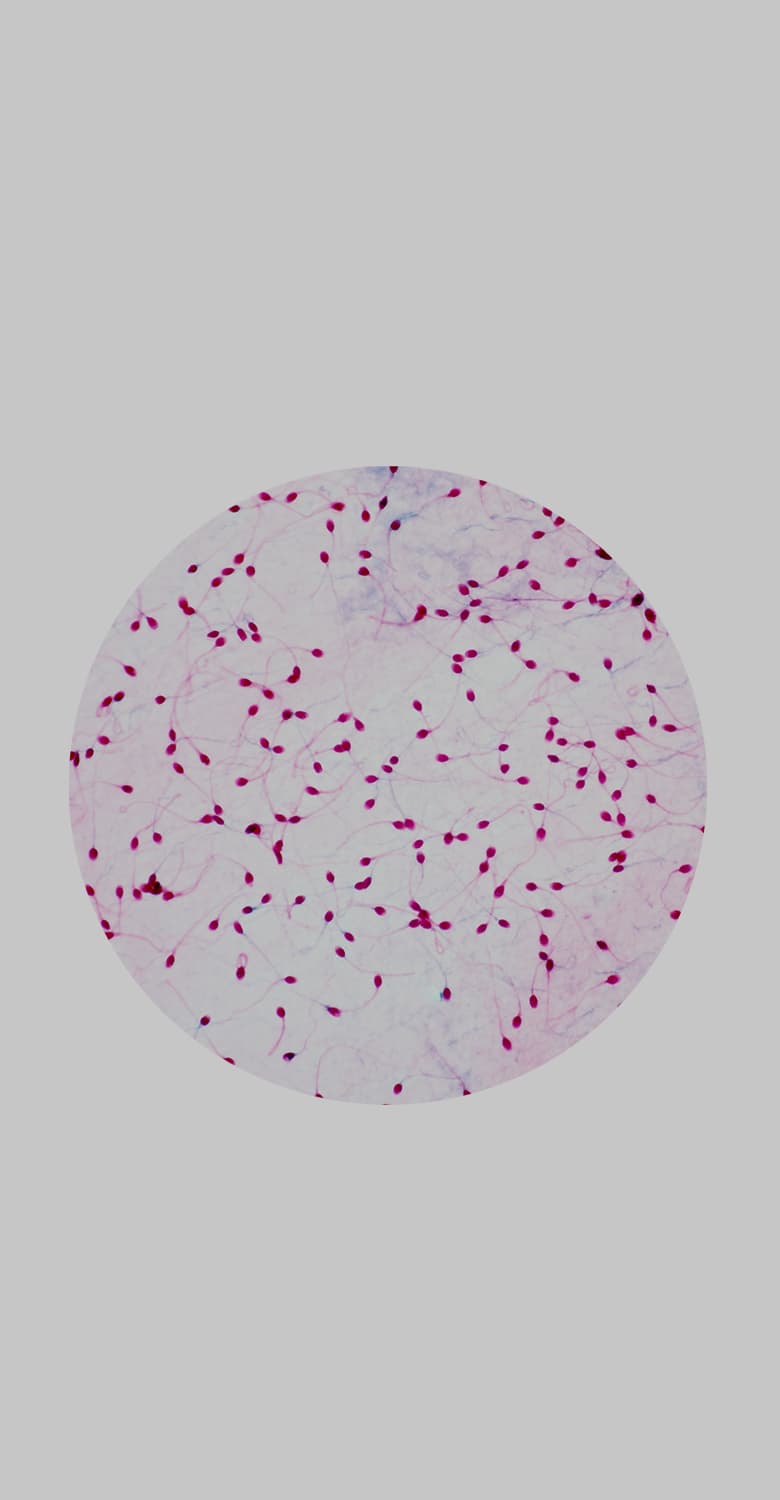

Спермограмма — это базовый анализ спермы, который позволяет оценить макроскопические (объем, ph и др.) и микроскопические (число сперматозоидов, а также подвижность и морфологию сперматозоидов) параметры.

Спермограмма — это анализ спермы. С помощью данного анализа можно оценить функцию половых органов и проходимость семявыносящих путей, а также определиться с дальнейшей тактикой обследования. С ее помощью можно выявить отсутствие сперматозоидов в эякуляте, недостаточную подвижность и концентрацию, заподозрить воспалительные заболевания половых органов и так далее.

Базовый анализ эякулята (спермограмма) учитывает важные параметры эякулята: объем, вязкость, концентрацию сперматозоидов, их подвижность и морфологию.